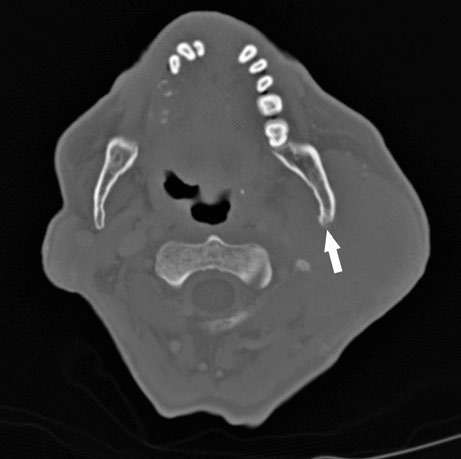

Dermal infiltration and bone involvement are findings that substantially alter the treatment plan. When there is clinical or radiological evidence of skin infiltration, the skin must be included as a target structure using bolus to ensure adequate surface dose. In cases with perioperative tumor spillage, the surgical scar also becomes part of the treatment volume.

Bone involvement requires specific assessment using bone windows on CT. The image shows periosteal reaction at the posterior aspect of the left mandibular ramus, suggesting direct involvement. When confirmed, the bony structure must be incorporated into the CTV with appropriate margin.

These findings highlight the importance of a thorough imaging study before simulation. The combination of soft tissue and bone windows on the same CT ensures that no tumor extension goes undetected.

When bone involvement is detected, the extent of mandibular irradiation must be carefully balanced against the risk of osteoradionecrosis (ORN). Including the involved bone segment with adequate margin is essential for local control, but extending CTV coverage unnecessarily into healthy mandibular bone increases ORN risk without oncologic benefit. The use of dose painting — delivering higher doses to the involved segment while limiting dose to uninvolved bone — can help achieve this balance when IMRT or VMAT techniques are available.